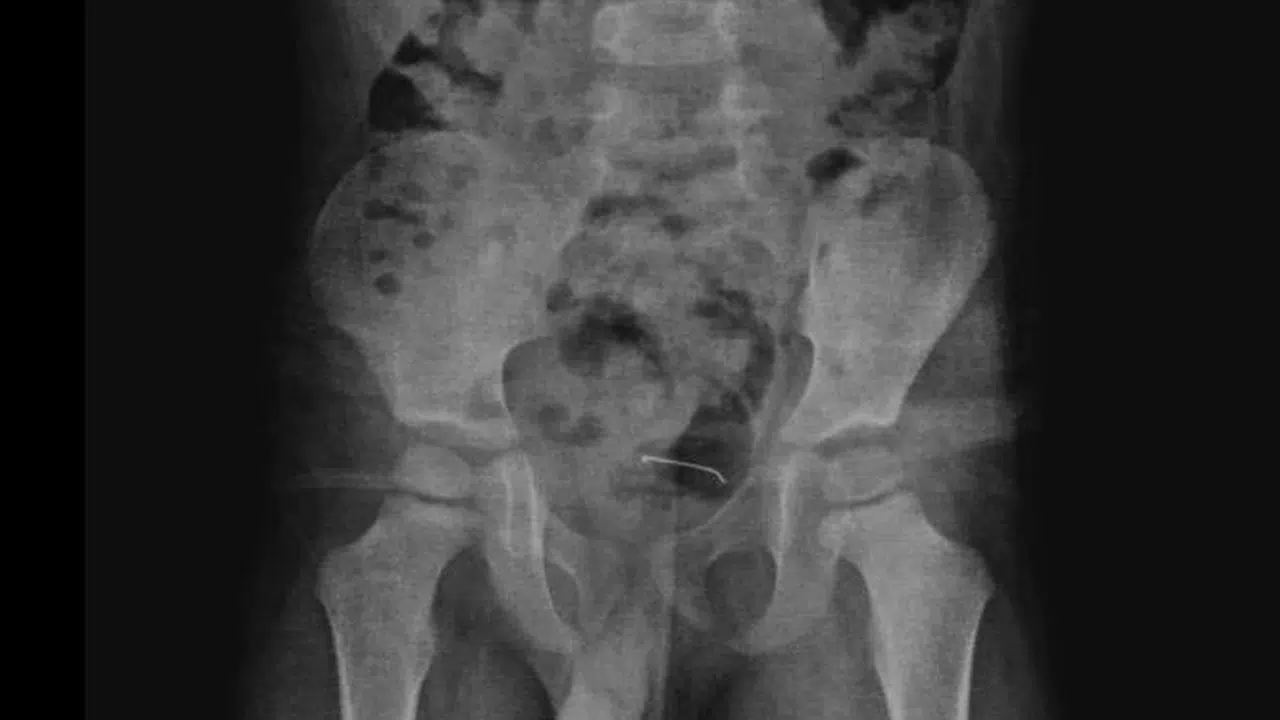

Özcan ÇİRİŞ/BİTLİS, (DHA)- BİTLİS'in Güroymak ilçesinde 5 yaşındaki çocuğun 9 ay önce yuttuğu, mesane duvarına yapışan toplu iğne, operasyonla çıkarıldı.

Güroymak'ta sürekli karın ağrısı şikayeti çeken 5 yaşındaki çocuk, ailesi tarafından çeşitli sağlık kuruluşlarına götürüldü. Sonuç alamayan aile, en son Tatvan Devlet Hastanesi'ne başvurdu. Burada çekilen röntgende, çocuğun mesane duvarında metal bir cisim olduğu belirlendi. 9 ay önce yutulan ve vücutta kalan 3 santimetrelik toplu iğnenin mesane duvarına yapıştığı tespit edilince ameliyata karar verildi.

Tatvan Devlet Hastanesi Çocuk Cerrahi Uzmanı Op. Dr. Tahsin Onat Kamçı tarafından gerçekleştirilen operasyonla, toplu iğne başarılı bir şekilde çıkarıldı. Gözlem altında tutulan çocuk, birkaç gün sonra taburcu edildi. Op. Dr. Tahsin Onat Kamçı "Cerrahi operasyonla 3 santimetre civarındaki toplu iğneyi çıkardık. Hastayı birkaç gün takipte tuttuk. Genel sağlık durumu iyi olan hastamızı taburcu ettik. Kesici ve delici cisimler çok tehlikeli. Bu gibi cisimlerin çocukların ulaşabileceği yerlere bırakılmaması gerekiyor" dedi. (DHA)